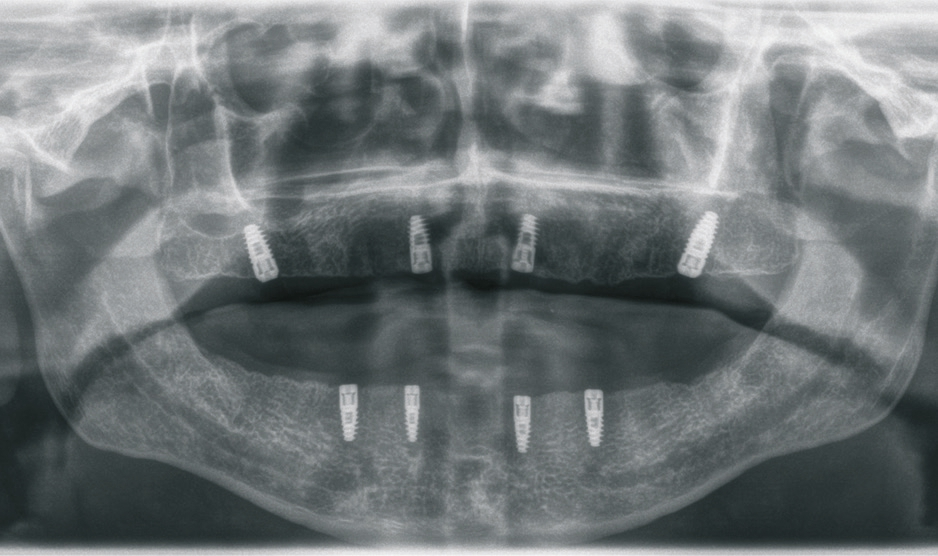

Der 49-jährige Patient trägt im Oberkiefer eine Prothese. Die Prothese im Unterkiefer hat ihn immer gestört, weswegen er diese schon länger nicht mehr getragen hat. Die Abbildungen 1 bis 3 zeigen den Ausgangsbefund. Während der Oberkiefer klinisch noch gut für Implantate geeignet erscheint, können im Unterkiefer schon Zweifel aufkommen. Bei genauerer Betrachtung des Oberkiefers in der Schichtaufnahme (OPG) kommt jedoch die Vermutung auf, dass der Knochen dünn sein könnte. Das war der Grund, warum wir vor der Implantation ein DVT erstellt haben.

Die Abbildungen 1 bis 3 zeigen die Ausgangssituation. Zuerst wurde nach der Herstellung einer Prothese eine Implantatplanung gemacht. In den Abbildungen 5 bis 7 zeigt sich die Herausforderung in diesem Fall: Geringe Platzverhältnisse für die Implantate im Knochen. Nachdem die erstellten Daten verschickt wurden, bekommen wir die Schablonen zurück (Abb. 8).

In Abbildung 12 ist die Einbringhilfe schön zu sehen. In Abbildung 13 kann man die relativ geringe Höhe der Schablone erkennen. Dadurch ist ein Implantieren auch im hinteren Bereich möglich. Gerne werden die Schablonen zu dick oder zu hoch gefertigt, so dass man schon ab dem 6er Bereich den Bohrer nicht mehr in die Schablone bekommt. Dann ist der Aufwand sehr groß, um damit zu implantieren. Aber hier ist dies erfreulicherweise möglich, da durch das C-Guide Konzept, eine ausreichende Führung der Bohrer gewährleistet ist. Trotz den niedrigen Hülsen ist eine Bohrführung gegeben! Nachdem nun alle Implantate eingebracht wurden, zeigt die klinische Kontrolle (Abb. 17) und auch das Abschlussbild im OPG (Abb. 18), dass die Implantate genau nach Planung gesetzt wurden (Abb. 19).